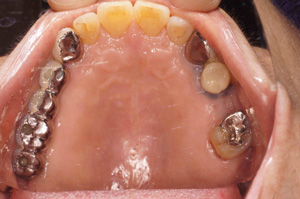

@K.K ‚³‚ñ@  72Î @—«@Žå•w      Žèp“ú@‚Q‚O‚O‚W”N@‚XŒŽ ‚X“úi‰Îj  ‰ºŠ{ƒm[ƒxƒ‹ƒKƒCƒhŽg—p@Ö¬“à’ÁÖ@•¹—p@

@@@@‰ºŠ{  All on ‚W@‘¦Žž‰×d

@@Rpl Tapered Rp‚SD‚O ~‚P‚O mm(‚S–{)@   Bmk MK‡V Rp‚RD‚V‚T ~ ‚WD‚T mm(‚R–{)       Bmk MK‡V Rp‚RD‚V‚T ~ ‚V mm